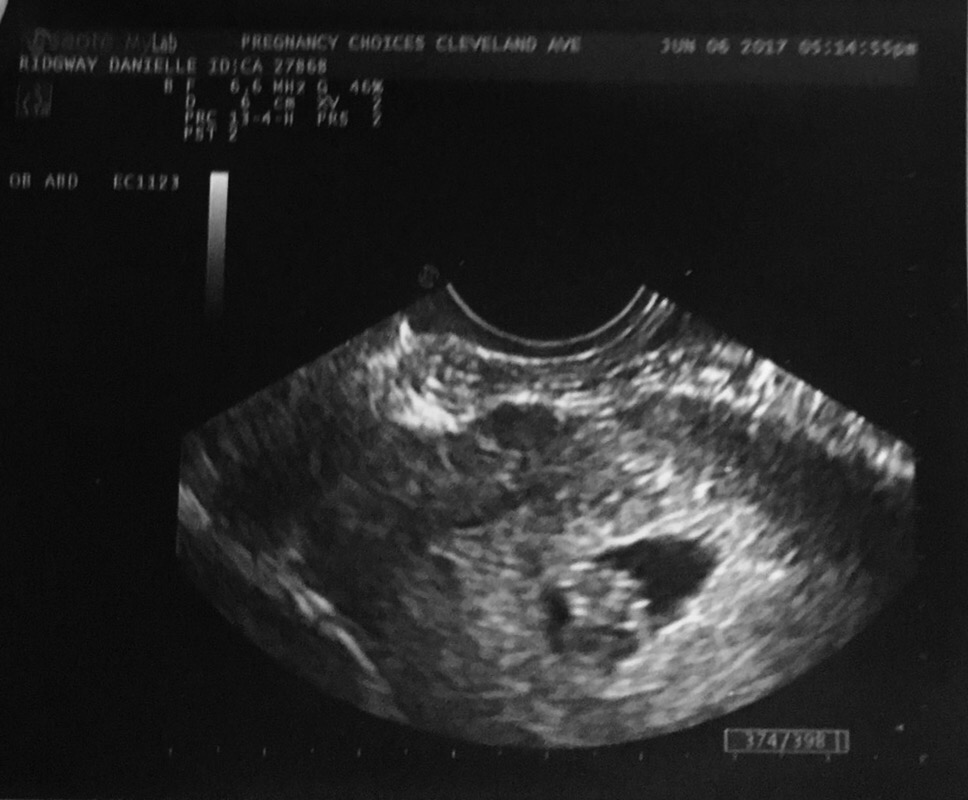

The past weeks were full of anxiety and guilt and joy for this new life inside of me. I’ve been sick to my stomach and craving avacados. Eleven days ago I even saw his or her’s strong heartbeat on the ultrasound screen. Ten perfect weeks of pregnancy.

I don’t know what’s going to happen now. In the blur of the conversations after those words, I know I’ll either miscarry naturally or have a D&C Monday. This weekend was supposed to be happy, I was going to announce to the rest of my family. Show them the baby’s ultrasound, have hope for the future.